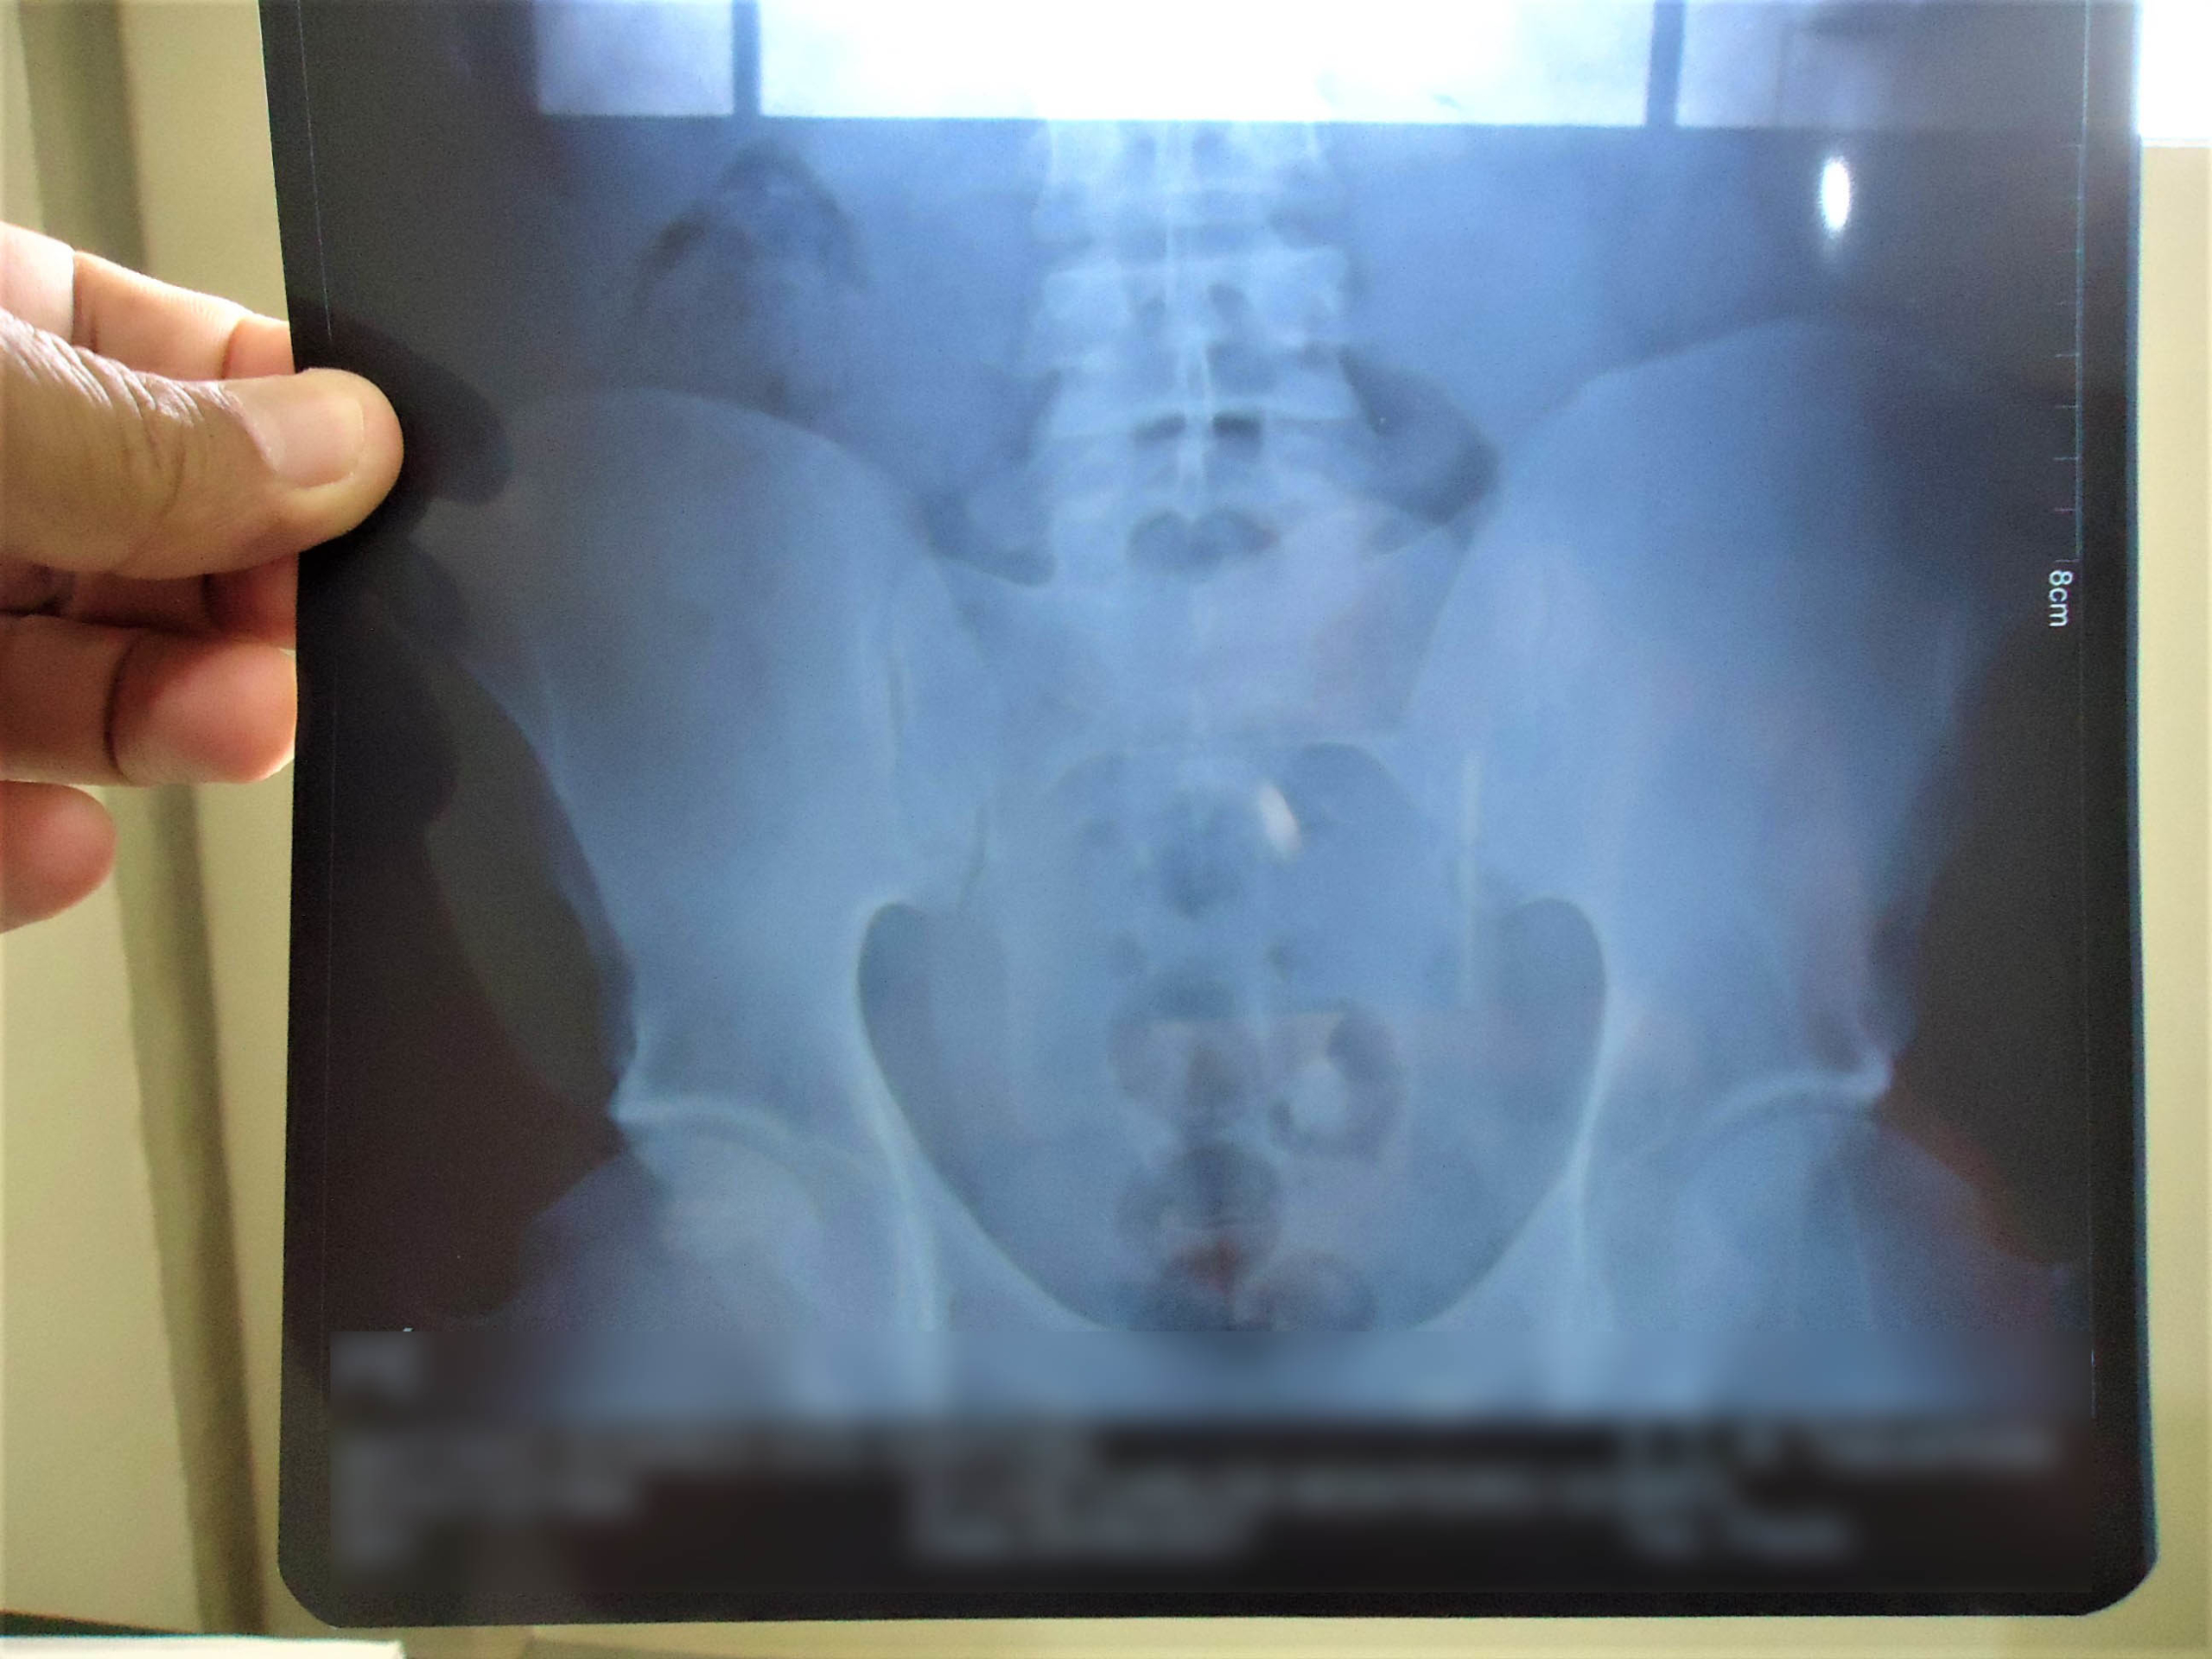

O flagrante aconteceu quando as mulheres passavam pelo aparelho (Body Scann), raio-x. Uma delas estava com um pacote de drogas no órgão genital, e as demais com entorpecentes no estômago. .